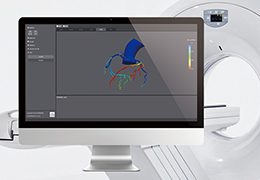

ART-Plan™ Artificial Intelligence Contouring